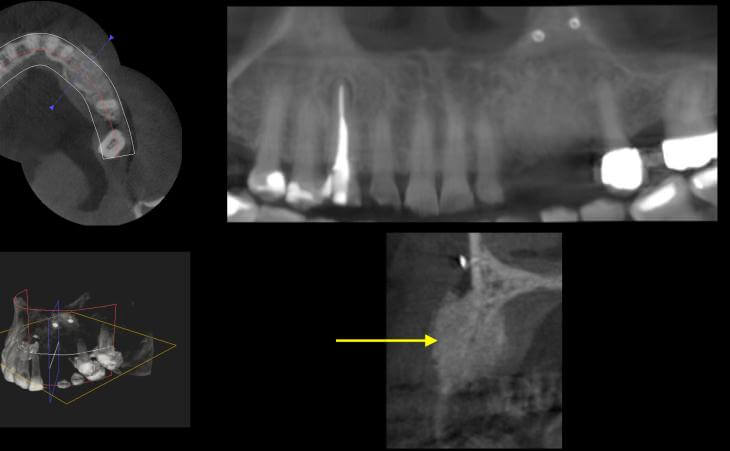

Resorbed Ridge Treatment Before

Resorbed Ridge Treatment Before Resorbed Ridge Treatment After

Resorbed Ridge Treatment After -

- thin ridge

thin ridge Pre surgical ct scan showed severely resorbed jaw bone

Pre surgical ct scan showed severely resorbed jaw bone After 4 months - a CT scan shows amazing bone volume regenerated

After 4 months - a CT scan shows amazing bone volume regenerated  Newly grown bone on CT scan

Newly grown bone on CT scan